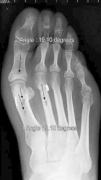

At this point, capsular plicature is performed in the traditional manner and the incisions are closed; the post-operative corrective bandages are as important as in percutaneous surgery. An orthopaedic shoe with an inverted heel is recommended and weight-bearing is not allowed for 2 weeks, at which time the sutures are removed and partial, gradual weight-bearing is begun starting at week 3. Patients can normally wear a non-orthopaedic shoe starting in week 6, at which time full weight-bearing is started (Figs. 1 and 2).

The 36 feet treated with this technique were evaluated and improvement of the IMA was achieved from 13.8° (range: 11–16°) to 7.6° in the immediate post-operative (range: 7–10°) with a mean improvement of this parameter of 6.2° (p<0.01). The HVA improved from a mean pre-operative value of 26.8° (range: 19–34°) to a mean value in the immediate post-operative period of 13.7° (range: 12–20°), showing a mean improvement of 13.1° (p<0.05). The results obtained at 15 days did not differ from the initial outcomes, although the results obtained starting at week 6 did improve, when the mean post-operative IMA was 8.6° and the HVA, 15.2°, with mean losses of 1° and 1.5°, respectively, in reduction. The values obtained at 3 months reveal a mean IMA of 9° and HVA of 16.2°, i.e. a loss of 1.4° in correction with respect to the initial IMA and 3.5° insofar as the initial HVA is concerned. At the 6-month, 1-year, and final follow-up visits, there were no variations as regards the IMA, but the HVA at the 1-year follow-up was 16.8° (Table 1). Therefore, there was an overall improvement at the final follow-up visit of 4.8° in the IMA (p<0.05), having lost 22% of the initial gain, and 10° in the HVA (p<0.05), having lost 27% of the initial gain (Table 2).

In our opinion, optimal radiological correction can be defined in terms of the initial classification (obtaining angle values within normal limits, namely IMA < 9° and HVA <11°) or in statistical terms (significant differences with a p value of at least <0.05). Insofar as the correction values obtained in this study are concerned, they demonstrate that this system makes it possible to achieve adequate correction of the IMA (both statistically and in “ideal” terms) and of the HVA (more statistical than classification, given that we manage to lessen the severity, albeit not bringing it back to normality, strictly speaking), comparable to other series that have made use of classical techniques34–36 (Table 1), although the immediate follow-up (up to 3 months) saw a 20% loss in the correction initially gained with the surgery. This does not increase over the subsequent follow-up visits and in no case has caused symptoms that have necessitated re-intervention for this reason (Figs. 3 and 4). In the same regard, if re-intervention is necessary because an osteotomy on the first metatarsal had not been performed, this would enable us to perform the pertinent technique without the problem of working on bone that has already been osteotomized.